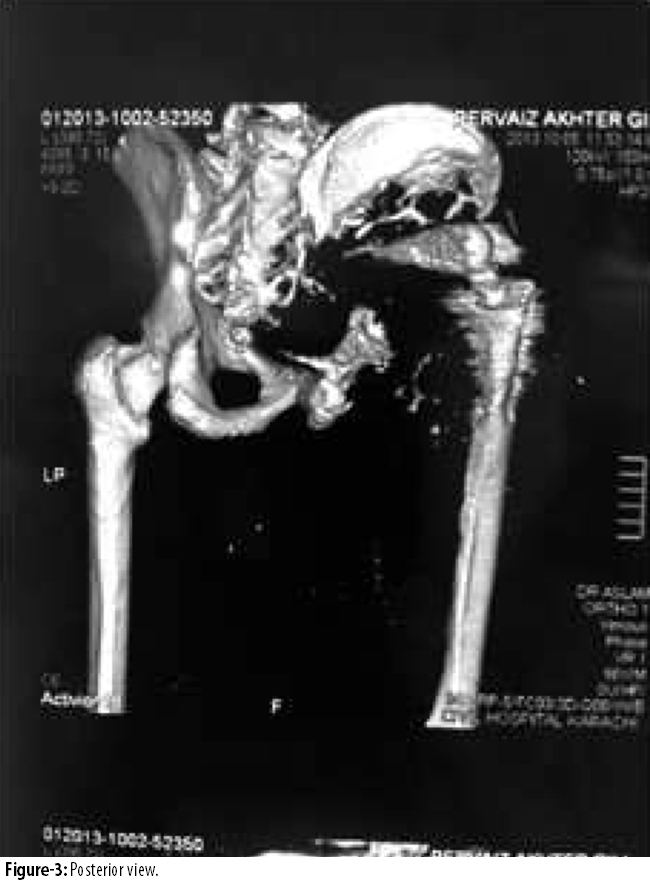

Posterior view showing eroded illium (Figure-3)